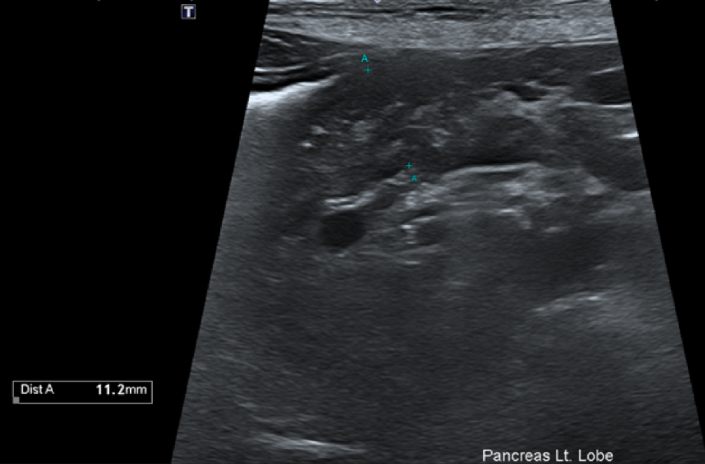

복부 초음파를 통해 복강 내 장기를 평가해본 결과 소장은 가스와 액체가 저류하여 운동성이 감소해 있었으며 췌장 실질이 비대되어 급성 췌장염 소견이 확인되고, 또한 급성 간염이 의심되는 상황이었습니다.

그림 3. 비대된 췌장 실질